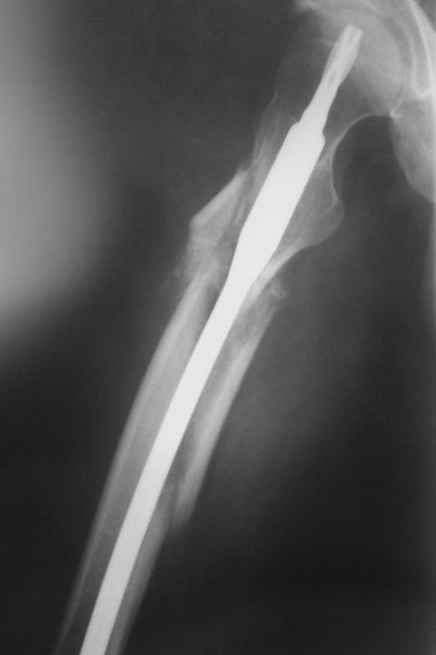

Практически единственное, что делает необходимым разрез для манипуляций с промежуточным отломком бедренной кости - это его "застегивание" в илиотибиальном тракте по типу пуговицы в петле.

Отломок, расположенный так, как на показанных рентгенограммах бедра, обычно на снимках в 1-2 мес. уже располагается ближе к диафизу и

включается в мозоль.

На операции я оставил осколок в области приводящих мышц бедра (ни пальпаторно, ни спицей сдвинуть не смог, "заклинило" насмерть). Фото спустя 2 месяца после операции (PFN).